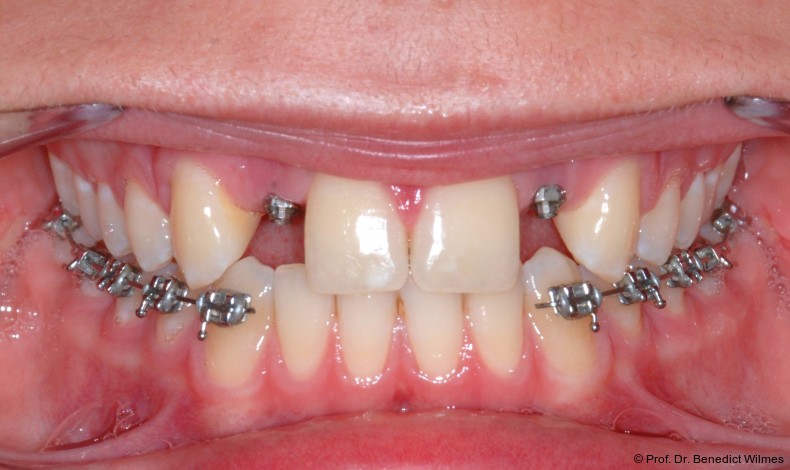

Ein 14-jähriger Patient wurde bei Aplasie der beiden oberen seitlichen Schneidezähne mit dem Ziel der beidseitigen Lückenöffnung kieferorthopädisch therapiert (Abb. 1a+b). Zum Ende der kieferorthopädischen Behandlung wurden zwei Miniimplantate in Regio 2er als temporärer Zahnersatz inseriert (Benefit System, PSM, 2 x 13 mm, Abb. 2a+b). Nach Abdrucknahme wurden Kronen auf den Peek-Abutments modelliert und diese mit Kunststoff auf die Abutments geklebt (Abb. 3a–d). In den Abbildungen 3 und 4 sind die klinischen und röntgenologischen Nachkontrollen innerhalb der nächsten achteinhalb Jahre dokumentiert. Man erkennt einen sowohl in der Höhe als auch in bukkopalatinalen Breite verbleibenden gesunden Knochen ohne Anzeichen einer Atrophie. Im Alter von 23 Jahren wurden die definitiven Implantate ohne die Notwendigkeit einer Augmentation eingesetzt (Abb. 5) und nach Einheilung prothetisch versorgt (Abb. 6a–e und Abb. 7a–c).

Bei einer elfjährigen Patientin fehlten bei Zustand nach Frontzahntrauma im Alter von neun Jahren beide oberen mittleren Schneidezähne (Abb. 8a+b). Als temporärer Ersatz wurden Miniimplantate (Abb. 9, 2 x 13 mm) eingesetzt und Kronen im Labor angefertigt, welche auf den Miniimplantaten verschraubt wurden (Abb. 10a+b). Die Miniimplantate wurden im Alter von 19 Jahren, also nach achtjähriger Nutzung (Abb. 11a+b), durch dentale Implantate ersetzt.